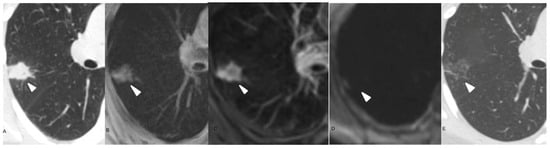

3.2. MR Findings